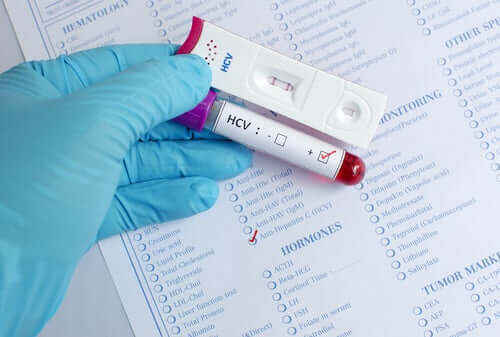

- C: 이 바이러스 입자는 혈액을 통해 사람들 사이에 가장 많이 전파된다. 일반적으로 적절한 보호 장치를 갖추지 않은 의료 전문가와 주사기를 공유하는 정맥 주사 약물 중독자가 감염될 수 있다. 대부분 환자는 만성 형태로 고통받고 있으며 B형 간염보다 더 자주 간 경변 및 간암으로 진행된다. 이 유형에는 백신이 없지만, 새로운 치료법으로 치료된 일부 환자들이 있다.

C형 간염은 혈액을 통해 전염되며 가장 심각한 결과는 간암이다.